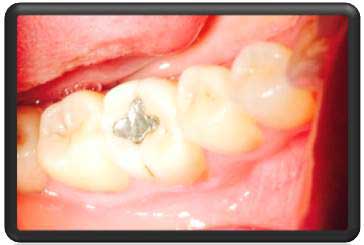

دندان شماره 6 پرکردگی آمالگام(سربی) قدیمی دارد |

در رادیوگرافی با کیفیت بالا توسط دستگاه دیجیتالی 3disk کمپانی امریکا. پوسیدگی وسیع در محل مشخص شده دیده شد. |

پس از بی حسی درمان با حذف پرکردگی قبلی آغاز شد |

پوسیدگی ها کامل حذف شدند |

بدلیل نزدیکی به عصب ماده ای که نقش عایق دارد در کف حفره گذاشته شد. این ماده ساخت کمپانی اولترادنت آمریکاست |

بعد از بستن قالب مخصوص voco حفره توسط کامپوزیتآلمان پرشد |